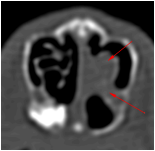

Pour déterminer l'origine et les caractéristiques de l'abcès, l'idéal est de réaliser un examen d'imagerie précis comme le scanner. Le scanner correspond à un examen radiographique en trois dimensions. Le traitement de choix est typiquement chirurgical et médical. Certaines de ces chirurgies peuvent être particulièrement complexes et nécessiter l'utilisation d'un endoscope.

Les abcès dentaires chez le lapin sont généralement secondaires à une malocclusion dentaire. Cette malocclusion entraine la formation de crevasses ou de pointes dentaires, formant dans un deuxième temps une surinfection puis un abcès. Dans certains cas, les abcès peuvent se former en arrière de l'oeil et faire ressortir l'oeil de son orbite. Le traitement de l'abcès passe d'abord par une évaluation précise des tissus infectés et de l'origine de l'infection (racine dentaire, corps étranger,...). Si cet étape n'est pas réalisée, les risques de récidives sont presque inévitables.

Abcès dentaires